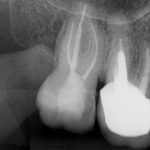

- Entretanto, o canal palatino por ser mais amplo foi instrumentado com a lima WaveOne Gold small, medium e large.

- Em seguida, os canais foram irrigados com hipoclorito de sódio 2,5% e foi utilizada a irrigação ultrassônica passiva para potencializar a limpeza dos canais.

- Para remoção do smear layer foi utilizado o EDTA.

- A obturação deu-se na técnica de onda contínua de condensação usando o cimento AHPLUS da Dentsply (Figuras 5, 6 e 7).

Nota-se que o tratamento foi conservador, com pouco desgaste de dentina pericervical, dando mais longevidade e manutenção da integridade da estrutura dental.

Figura 2 Figura 3 Figura 4 Figura 5 Figura 6 Figura 7